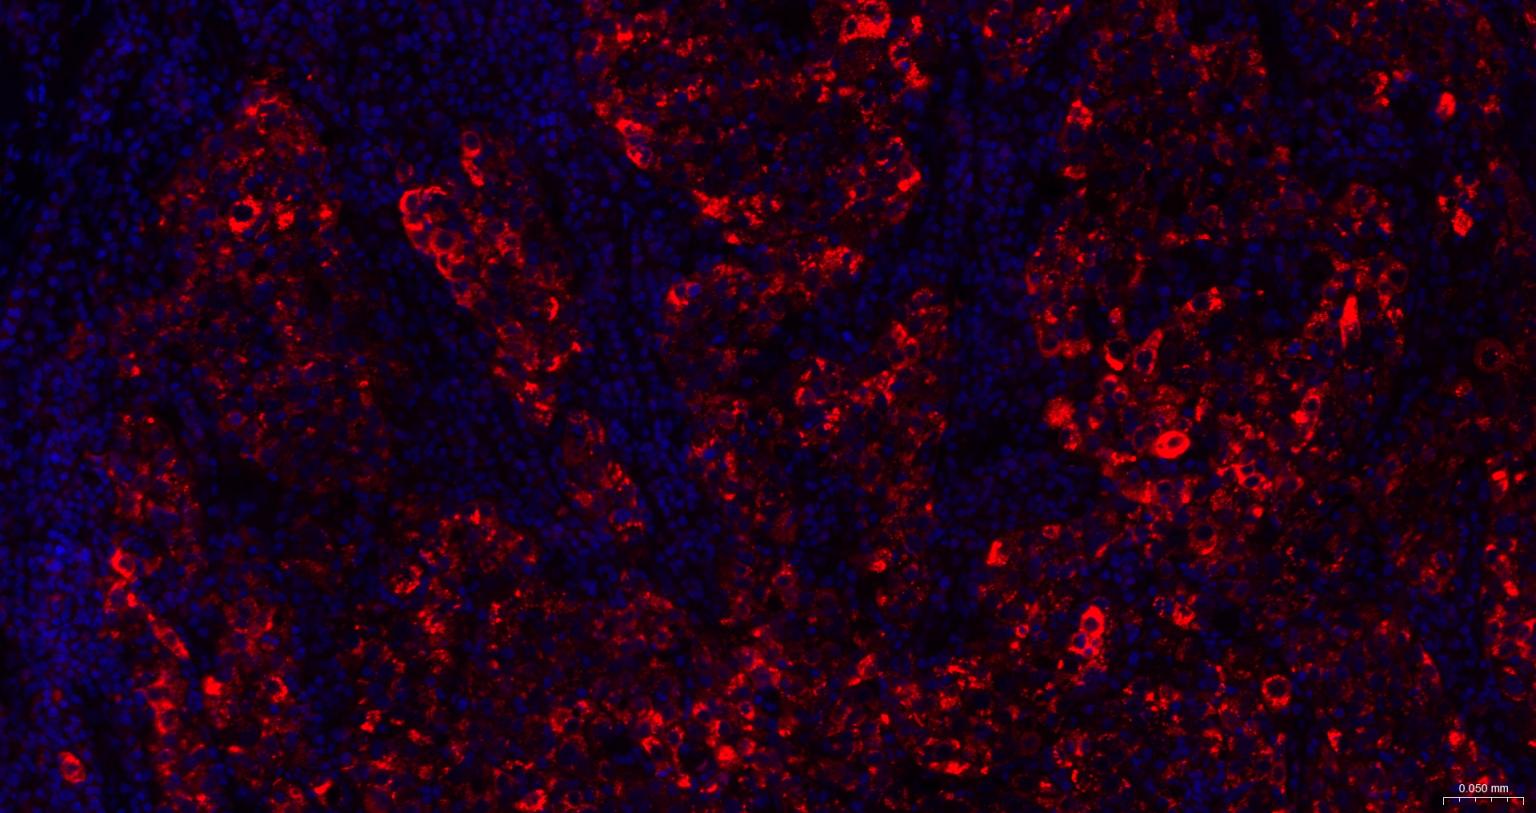

Paraformaldehyde-fixed, paraffin embedded Human Gastric Cancer; Antigen retrieval by boiling in sodium citrate buffer (pH6.0) for 15 min; The section was incubated with SQSTM1/p62 Monoclonal Antibody, Unconjugated (bsm-60709R) at 1:200 overnight at 4°C. Followed by conjugated Goat Anti-Rabbit IgG antibody (Red, bs-0295G-BF594), DAPI (blue, C02-04002) was used to stain the cell nuclei.